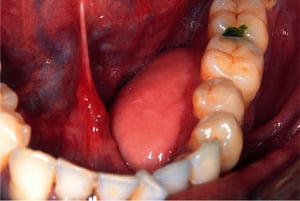

この写真には,口腔内に生じたガマ腫(中央)の拡大像が写っている。ガマ腫は口底に生じる粘液嚢胞である(一般的に口腔内の他の部位に生じる粘液嚢胞よりも大きい)。ガマ腫でみられるムチンの産生源は,通常は舌下腺(ときに顎下腺管)である。

粘液嚢胞(粘液貯留嚢胞およびガマ腫)は無痛性かつ良性であり,嚢胞性または偽嚢胞性の唾液腺粘液の貯留による口腔内腫脹である。しばしば外傷に起因する。圧倒的に多い病変である粘液嚢胞は,ほとんどの場合,下唇側方の内側に発生し,粘膜下に流出したムチンの存在により,しばしば青みがかった半透明色である。通常これはうっかり(下)唇を噛んだ結果生じ,小唾液腺からの唾液の流れが閉塞されることによって発現する。大半の粘液嚢胞は1,2週間で消失する。ガマ腫は大きく,通常,青みがかった粘液嚢胞であり,口底に生じる。治療は外科的切除である。